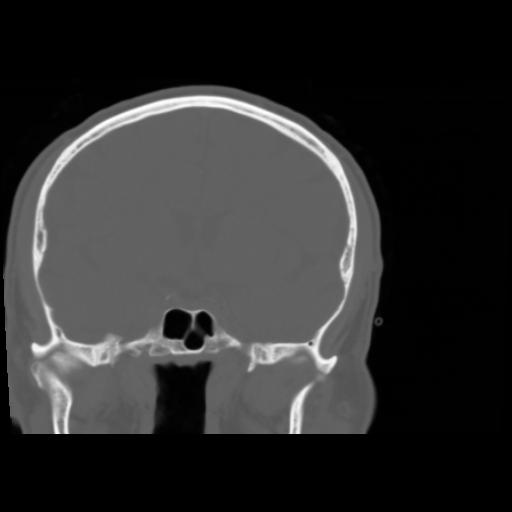

5 CEREBRO,,Coronal,3.000,CEREBRO,Coronal,